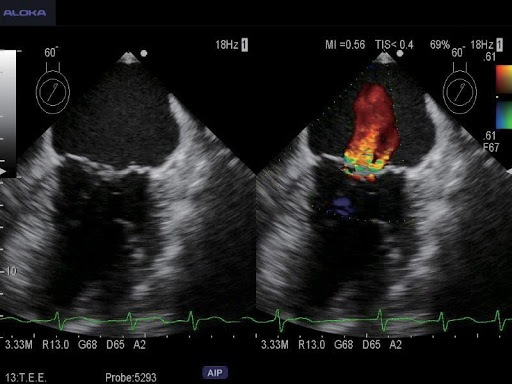

Экспертные функции подойдут для продвинутой диагностики сердечно-сосудистой системы, органов малого таза, вычислений показателей гемодинамики и других узких специализаций. Современные технологии работы с изображениями дают превосходное качество и позволяют извлечь максимум информации. Серошкальная визуализация, допплеровское цветовое картирование кровотока, а также спектральное допплеровское исследование кровотока, которые поддерживает система, позволяют оперативно провести качественные и количественные оценки.

- кардиологические (включая ТЭЭ)

Экспертная кардиология:

- Фазированные кардиологические датчики для взрослых, детей и новорождённых

- Чреспищеводные датчики для всех возрастов

UST-52105 – Датчик для проведения эхокардиографических исследований взрослых. Также подходит для транскраниальной допплерографии.

UST-5293-5 – Чреспищеводный датчик с возможностью поворота плоскости сканирования. Предназначен для эхокардиографических исследований взрослых.